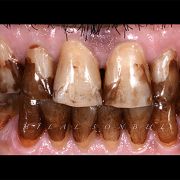

The patient was complaining of heavy stain and multiple faulty restorations. Considering the age in analyzing the teeth shape, contour and color play a vital role in success. Root canal treatment was done for the anterior teeth (Dr Khalid Merdad). Veneers and crowns @perlasmile lab.